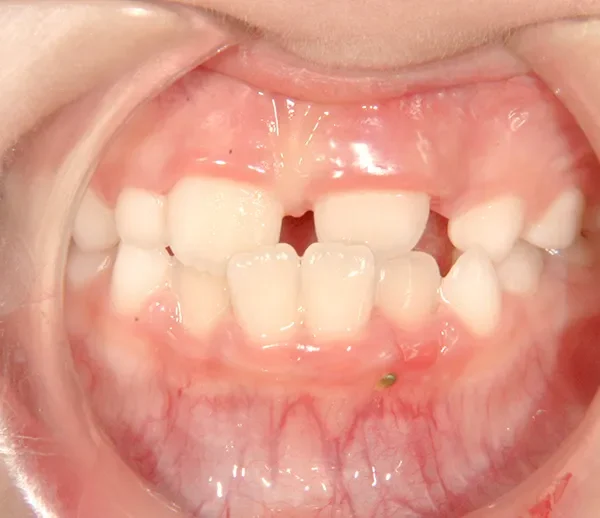

初診時年齢 小学校1年生 (男性) 主訴 すきっ歯・ガタガタ・受け口

診断名 叢生・反対咬合・空隙歯列 装置名

特徴 ゆがんで生えている

状態 永久歯が生える隙間がない(叢生)

受け口(下顎前突/反対咬合)

すきっ歯(空隙歯列)

上の前歯が下の前歯より後ろに入って、受け口になっています。

下の歯は永久歯の生えるスペースがないので、オリジナル矯正装置で受け口を治して、永久歯の生えるスペースを作りました。